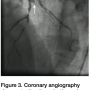

Approximately 25 minutes post-procedure, the patient developed severe chest pressure with lateral ST elevations. The patient was taken back emergently to the catheterization laboratory, where angiography demonstrated 100% thrombotic occlusion of the RI at the proximal edge of the recently placed stent (Figure 3). The patient was re-bolused with bivalirudin, followed by infusion and activated clotting time (ACT) after bivalirudin administration was confirmed to be 397 seconds. Laser atherectomy was performed using a 0.9 mm excimer laser

coronary atherectomy catheter (Spectranetics) (Figure 4) with multiple runs, followed by aggressive angioplasty using a 2.75 mm non-compliant balloon and adequate stent expansion confirmed by intravascular ultrasound (IVUS; Boston Scientific). Final angiogram again demonstrated good result with TIMI-3 flow (Figure 5) and resolution of ST changes and chest pressure.